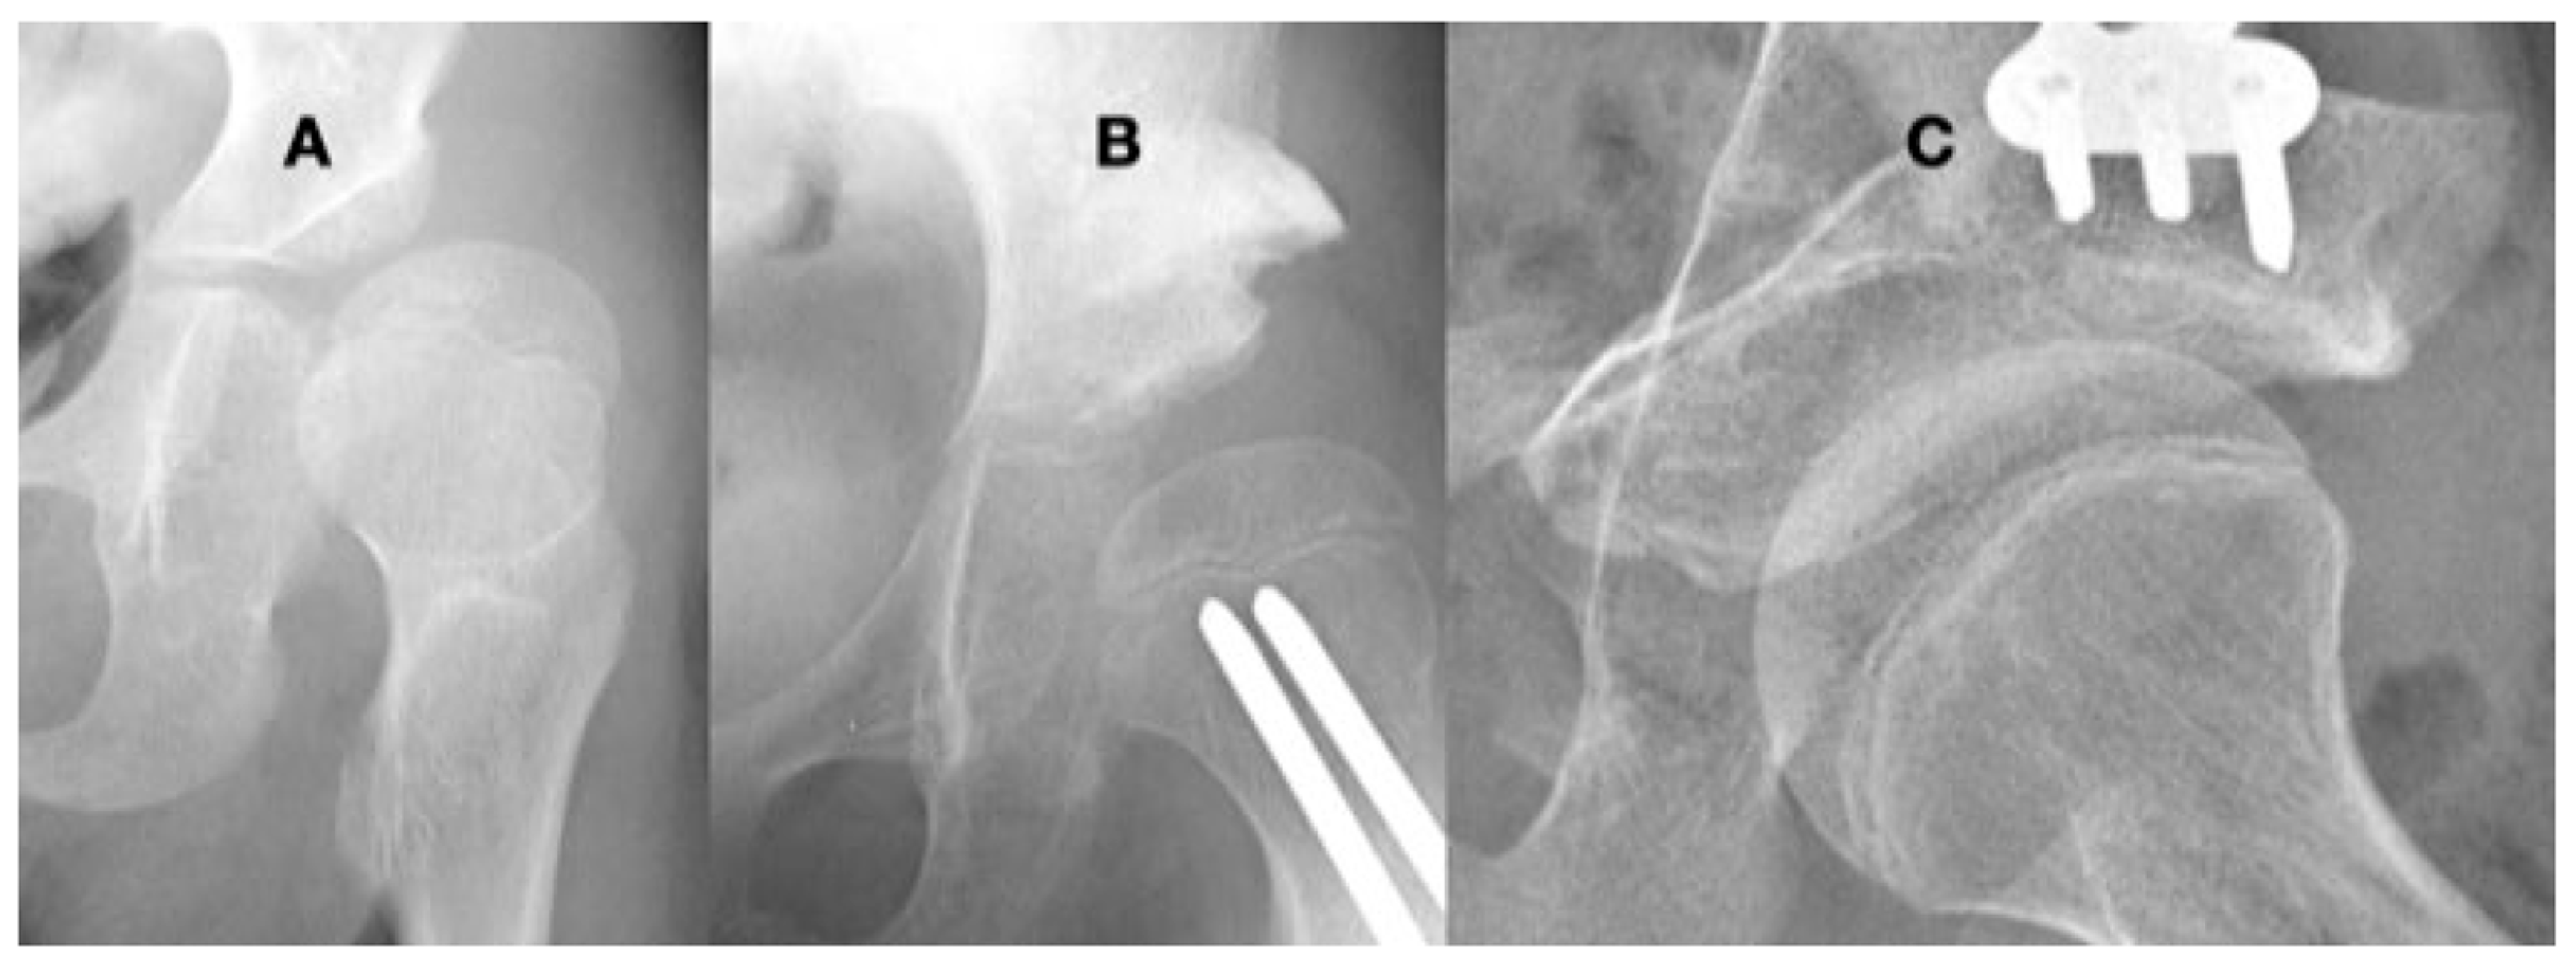

3.3.1. Impact of Abnormal Motor Function on Hip Development in Ambulatory Children

3.3.2. Pathology of Hip Development in Nonambulatory Children